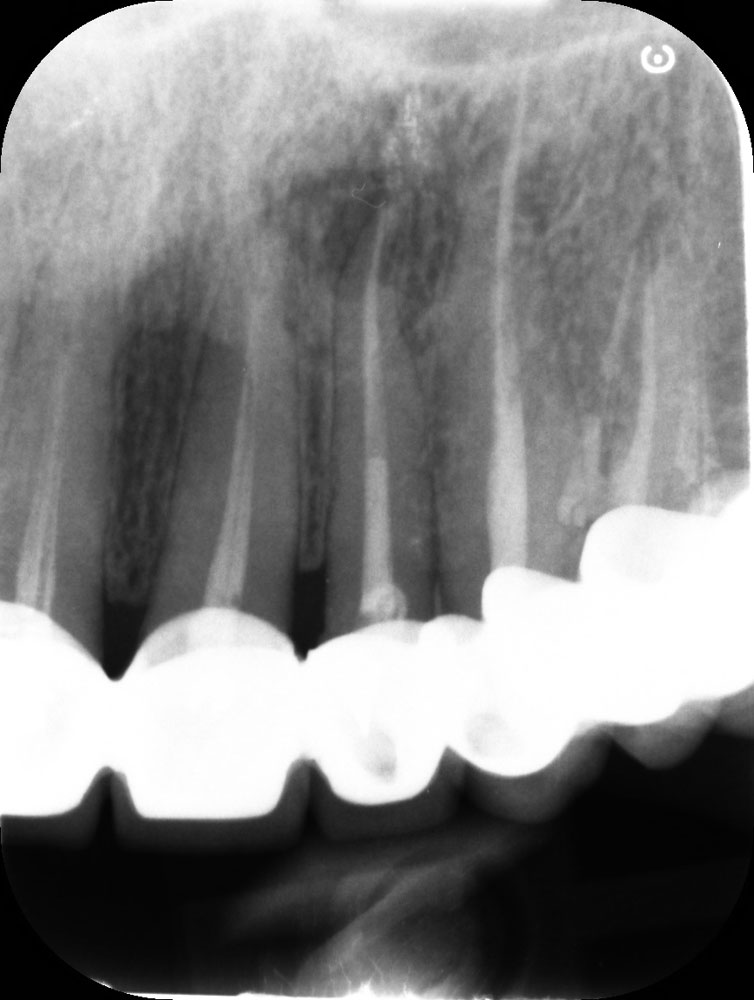

Root canal treatment is a procedure used to remove infected or inflamed pulp from inside a tooth. If left untreated, this condition can lead to a painful abscess. By performing root canal treatment, the tooth can often be saved, avoiding the need for extraction and preserving your natural smile.

In some cases, there may be no noticeable symptoms, but untreated pulp infection can eventually lead to pain, swelling, and loss of supporting bone.